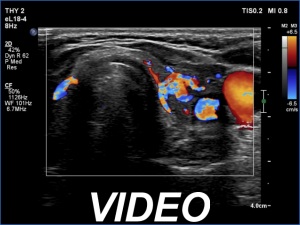

Initial examination (first row of images):

Clinical presentation: A 47-year-old woman was referred for evaluation of complaints suggesting subacute thyroiditis. She has had neck complaints and subfebrility for a month. First, the right lobe became painful, two weeks later the pain migrated to the left lobe. Non-steroid anti-inflammatory drug and 20 mg methimazole were administered by the GP. The complaints ceased 10 days before the present examination. A week after the beginning of the complaints, the CRP was 107 mg/L, the FT4 39.1 pM/L.

Palpation: Both lobes were firm, the left lobe was a bit tender on palpation.

Laboratory examination: TSH 0.01 mIU/L, FT4 17.9 pM/L, CRP 3.0 mg/L.

Ultrasonography: Both lobes were moderately hypoechoic and had a cloudy appearance. Both lobes had discrete lesions without oncological importance. The vascularity was decreased.

Diagnosis: subacute, granulomatous de Quervain's thyroiditis.

Suggestion. Ceasing the thyrostatic therapy and the anti-inflammatory drug. Repeat examination in three months, if the complaints would recur, at once.